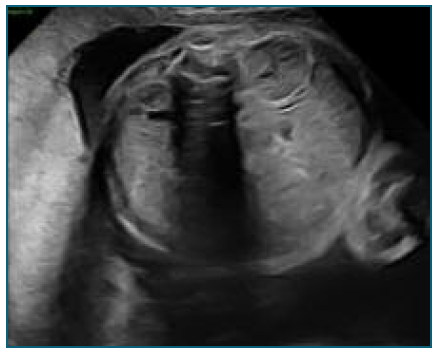

The shunt placement, at 32 weeks and 3 days (Figure 2), occurred without complications, although laborious due to fetal positioning, pleural fluid was collected for analysis. The shunt appeared to be functioning with clear improvement in effusion (Figure 3).